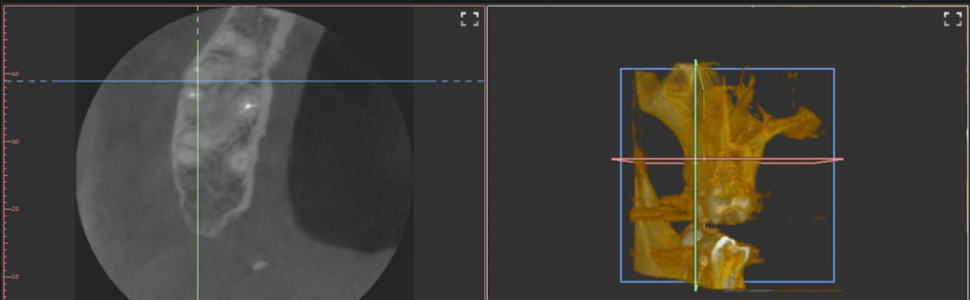

Radiological imaging is a part of diagnostics during endodontic treatment. A periapical X-ray is a basic tool, helpful in proper diagnosing to choose the appropriate treatment, controlling it during the procedure and as a feedback, in order to observe the changes in the periapical region. However, when the fundamental scheme seems to be insufficient, a cone-beam computed tomography (CBCT) may be favorable. This imaging technique allows to examine the third dimension of the treated region, which might reveal a previously unrecognized periapical lesion or be crucial to diagnose an improper endodontic treatment.